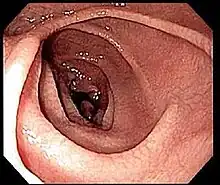

Most people with coeliac disease have a small intestine that appears to be normal on endoscopy before the biopsies are examined. However, five findings have been associated with high specificity for coeliac disease: scalloping of the small bowel folds (pictured), paucity in the folds, a mosaic pattern to the mucosa (described as a "cracked-mud" appearance), prominence of the submucosa blood vessels, and a nodular pattern to the mucosa.[96]